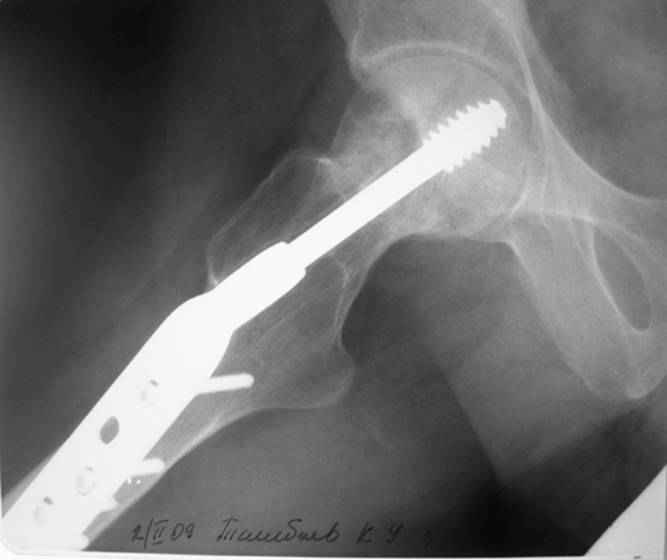

Больной Т. 1966 г.р.Травма 28.06.2007. Прооперирован в г. Бишкек, Оп:

Остеосинтез правого бедра системой DHS. В последующем беспокоили

периодические боли в правом тазобедренном суставе с иррадиацией в

коленный сустав в область передней поверхности правого бедра. Лечился

амбулаторно с незначительным эффектом.

В 07.04.2008 по 08.05.2008 года лечился в госпитале ГУВД и СО в

стационаре с Срастающийся перелом шейки правого бедра в условиях

фиксации системой DHS – боли уменьшились.Боли обострились 03.02.2009

внезапно, госпитализирован.

Результат - Псевдоартроз шейки правого бедра (имеются косвенные

признаки разрушения спонгиозной части головки бедра)Планируется -